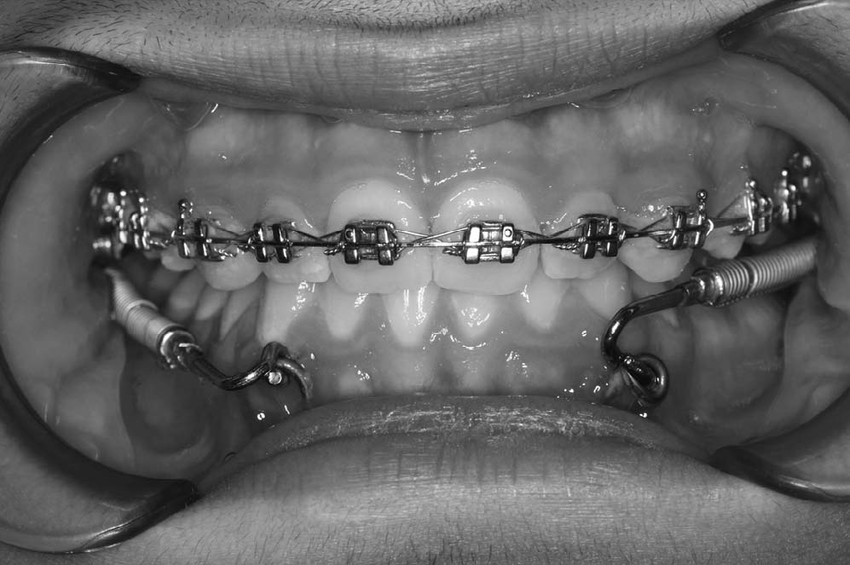

All patients got 0.018″ Roth brackets. But like filter coffee, how you serve it makes all the difference âđ

- MA-Forsus: Only upper arch teeth got bonded (minimalist vibes)

- C-Forsus: All maxillary and mandibular teeth bonded, second molars too (go big or go home)

For C-Forsus kids:

- Maxillary molars got the headgear tubes

- Mandibular archwire joined the fun between canine & premolar

(Simple setup, but no drama-free guarantee)

For MA-Forsus champs:

These kids got a full VIP treatment, surgical-style đĽđŞ

đŞ Miniplate Insertion:

- Under local anesthesia (brave heroes, truly)

- A 10mm horizontal incision ~5mm above the gum line

- Mucoperiosteal flaps lifted (like dosa batter, gently and with care)

- Two miniplates placed with:

- 7mm screws at the top

- 9mm screws at the bottom

- 1.5â2mm space between plate and mucosa (no one wants sore spots, okay?)

Sutures out on day 7, and boomâready for action! đĽ

Then, Forsus FRDs were attached like this:

- Upper part: maxillary molar tubes

- Lower part: miniplate long arms (anchorage of the gods, I tell you!) đ